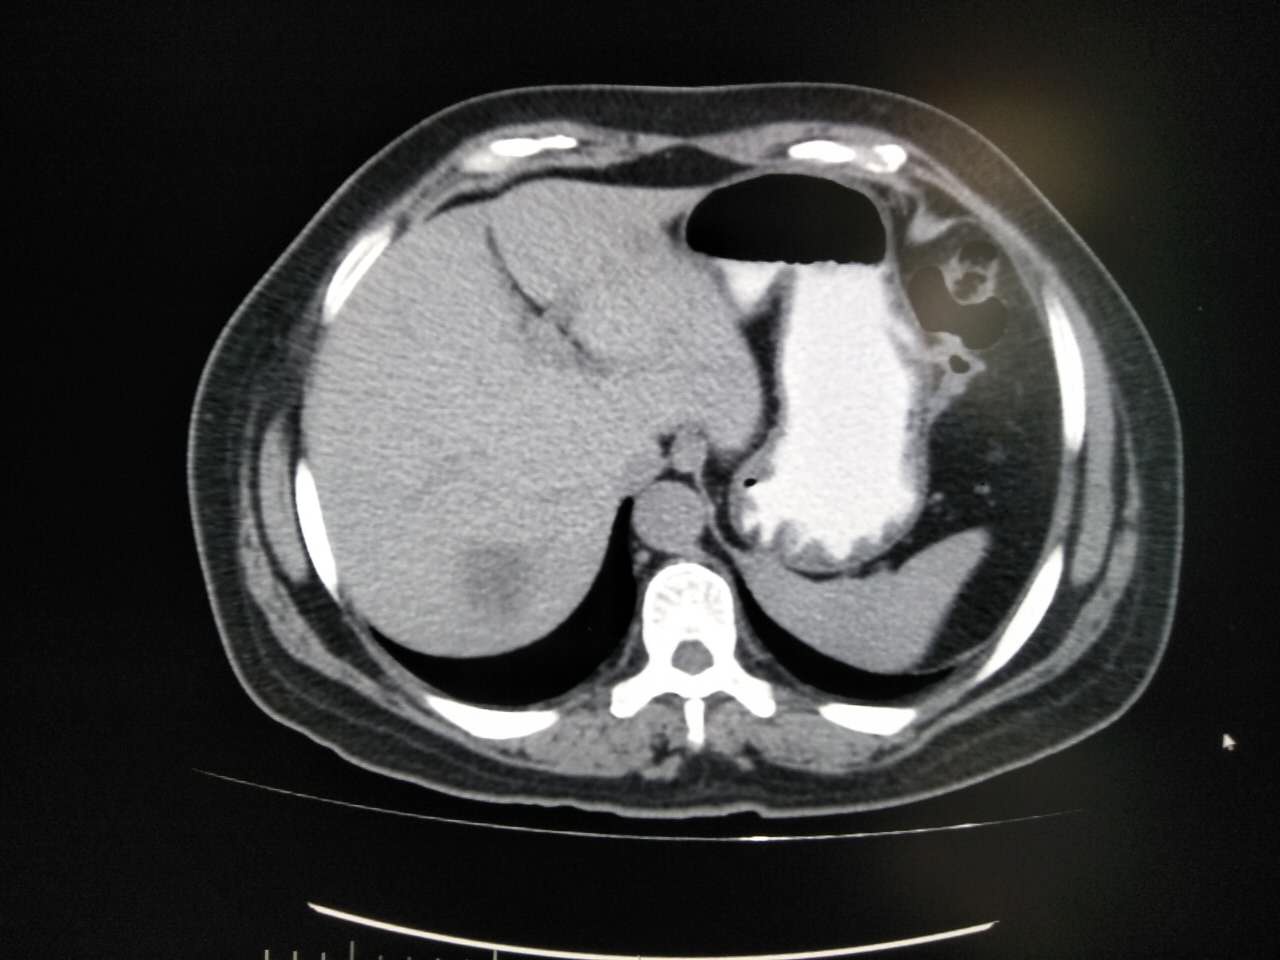

以下几例是胃肠道对比度较好的例子,可以清晰显示胃肠壁有无病变。